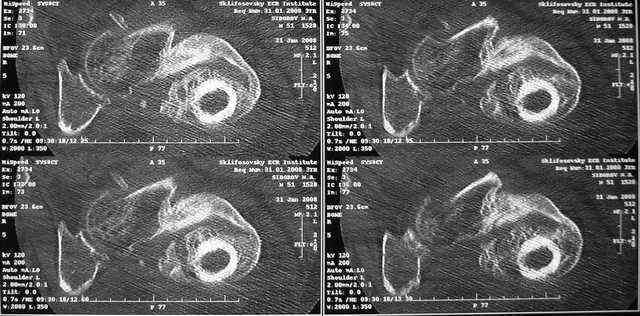

Какие были движения в суставах до наложения аппарата? Нет ли КТ с 3D?

Дорогие Александр Николаевич и Алексей Владимирович, вы конечно же правы. Если планировать остеосинтез, то надо сделать более точную репозицию. Планируем этим заняться в ближайшие дни. Алексей Владимирович, движения в тазобедренном суставе были в пределах 10-20 гр. Завтра попрошу у врачей из КТ сделать 3D реконструкции.